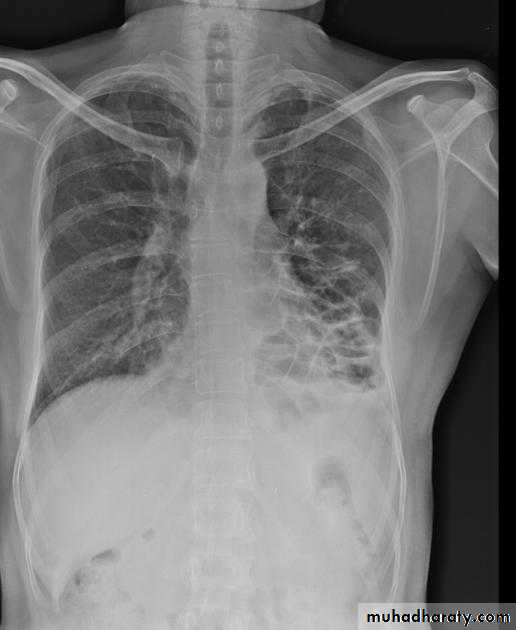

Post primary TB broncho pneumonia cotton wool signBilateral patchy opacities of the upper lobes of the lungs, cotton wool sign.

61.post primary TB notice upper apical Broncho pneumonic shadow

Bilateral Patchy opacification of the lungs involving upper zones, a cavity can be seen in the right uper lobe( 3rd photo)bronchopnemonia